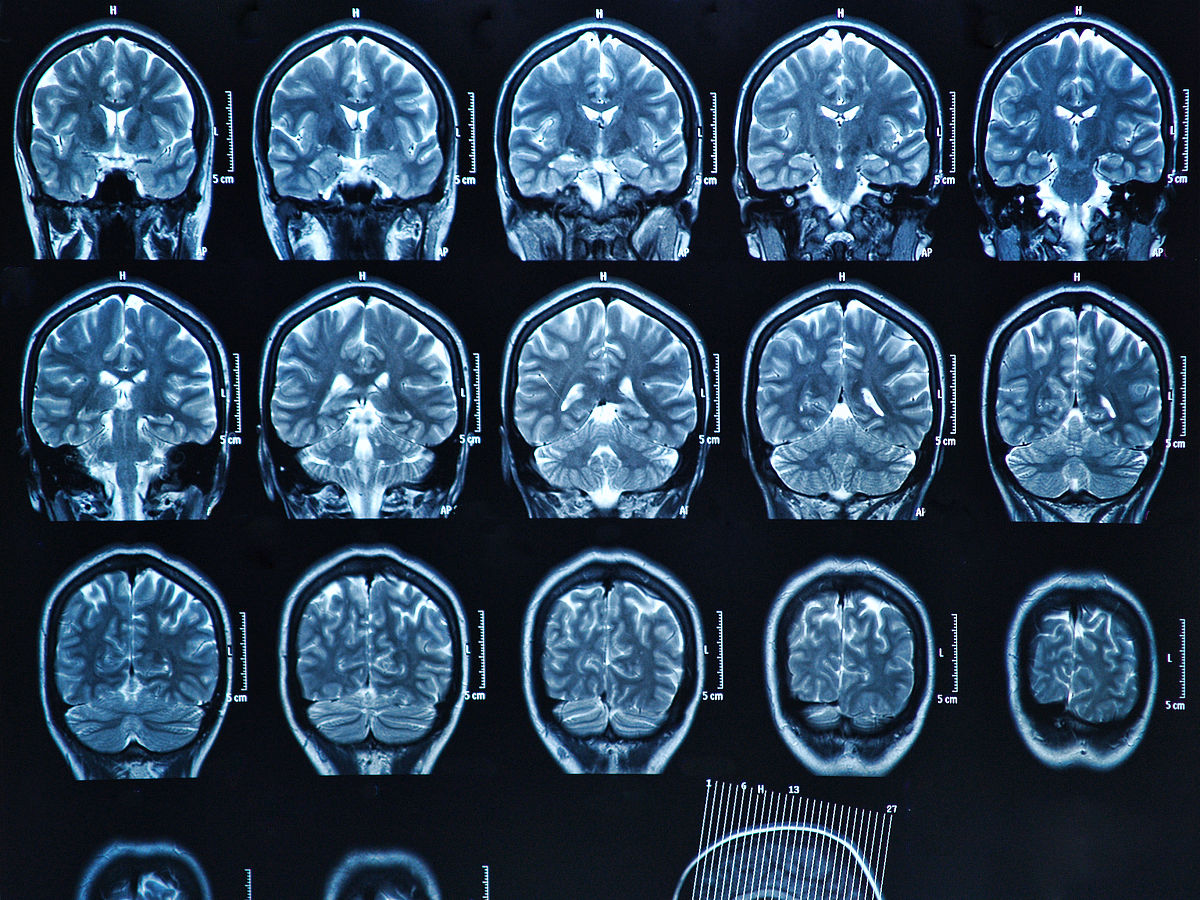

1. 神经元活动和代谢状态的评估:PET可以测量脑内神经元的活动和代谢状态,从而评估神经系统的功能状态和损伤程度。在痴呆型神经退行性疾病早期,神经元活动和代谢状态的变化可能比结构损伤更早出现,因此PET可以提供更早的诊断信息。